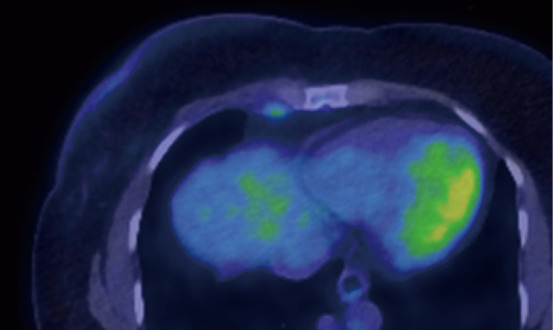

Key content and findings: Improved imaging techniques, with positron emission tomography-computed tomography and magnetic resonance imaging, have led to increase in the identification of IM lymphadenopathy, yielding surgical staging of the IM nodes nearly obsolete. While IM nodal metastases may play a role in overall survival (OS), it has not been demonstrated to be an independent risk factor for increased locoregional recurrence. IM nodal irradiation (IMNI) therapy has been a mainstay in the treatment of IM disease in the context of breast cancer. IMNI has demonstrated improvement in OS and risk of distant recurrence. Wide variations in radiation practices for patients with IM lymphadenopathy exist internationally, highlighting the lack of clear data driven consensus guidelines.